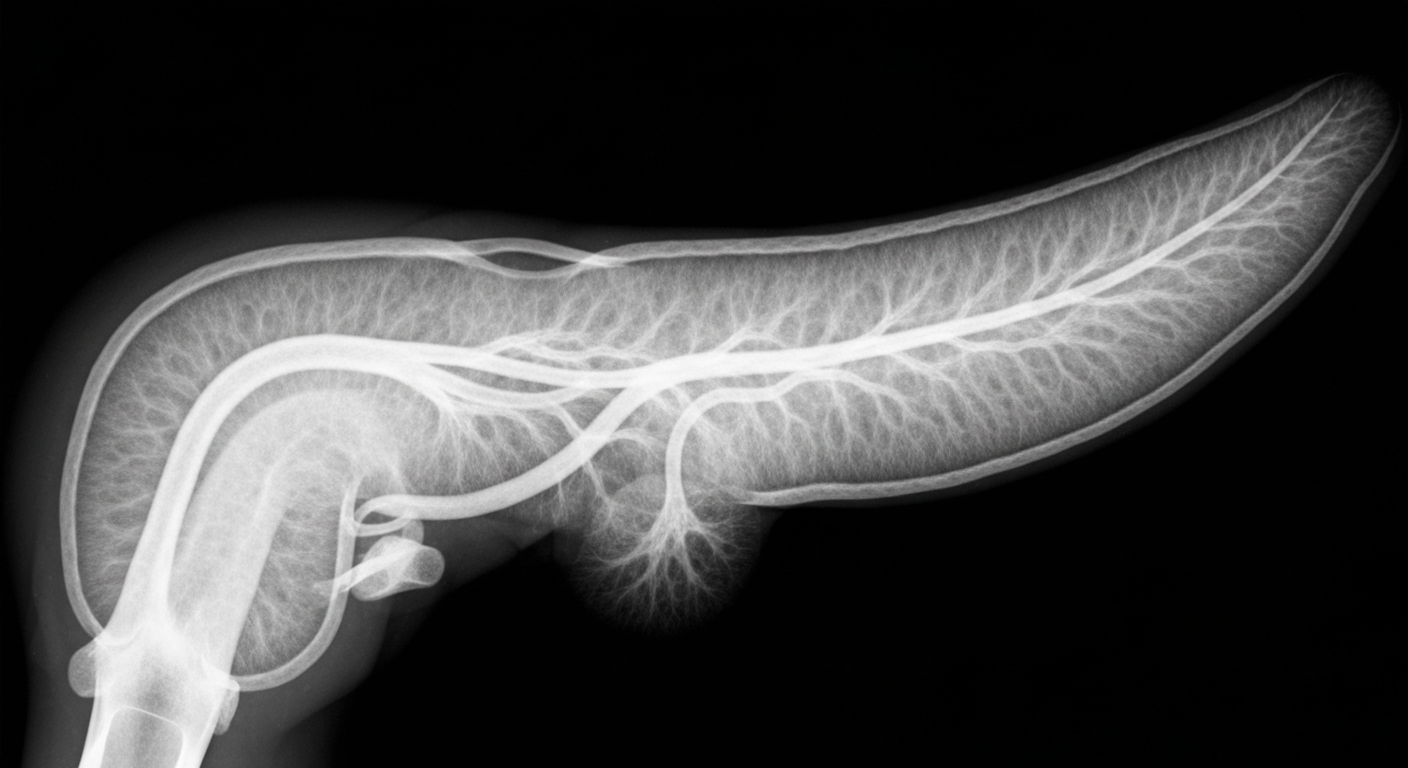

New Pancreatic Cancer Pill Shows Promise of Longer Survival

The treatment targets specific genetic mutations and could significantly improve outcomes for patients.

A new targeted treatment for pancreatic cancer offers hope of significantly extending survival time for patients with certain genetic mutations.Oklahoma City TodayA new pancreatic cancer treatment pill has been shown to nearly double the overall survival time for patients, according to the drug's manufacturer. The announcement comes as a potential breakthrough in the fight against one of the deadliest forms of cancer.

Pancreatic cancer has historically had very poor survival rates, with a 5-year survival rate of only around 10%. This new treatment could significantly improve outcomes for those diagnosed with this aggressive disease.

The drug company behind the new pancreatic cancer pill claims the treatment has demonstrated a median overall survival time of nearly 2 years, compared to just over 1 year for standard of care. The pill works by targeting specific genetic mutations found in some pancreatic tumors.

- The drug trial results were announced on April 13, 2026.

This new pancreatic cancer treatment represents a significant breakthrough, potentially doubling survival time for patients with this deadly form of cancer. If approved, it could transform the outlook for those diagnosed with pancreatic tumors harboring the targeted genetic mutations.